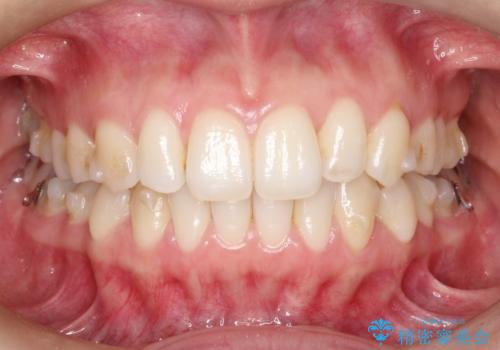

抜歯なし/インビザラインによるマウスピース矯正にて治療を行いました。

内側に入り込んでしまっている歯を出してくることに非常に時間がかかりましたが、一度歯を歯茎の方へ押し込みそして前へ出してくる2段階の治療を行いました。